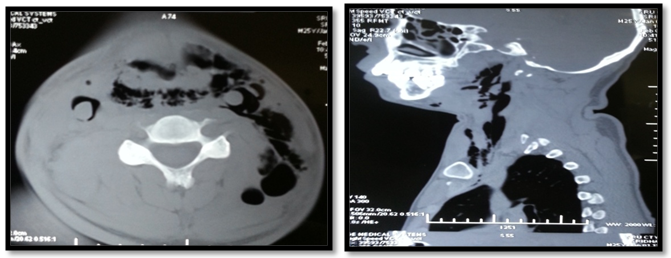

The second patient is a 58year male who came to the emergency room with alleged history of RTA following which he developed difficulty in swallowing and spitting out blood stained sputum. Examination revealed subcutaneous emphysema and tenderness over the laryngeal frame work. CT-neck plain showed extensive emphysema of neck with extension into the superior mediastinum (Figure 1) and fracture of thyroid cartilage at the midline with mild lateral displacement of the right side ala (Figure 2). He was admitted in the intensive care unit and was monitored for 24hours after which tracheostomy followed by neck exploration and laryngeal stabilization under general anesthesia was performed where in the fragmented thyroid cartilages were sutured. He was on ryles tube feed for 2months following which he was decannulated and ryles tube was removed.

Figure 4 Fracture of thyroid cartilage at the midline with mild lateral displacement of the right side ala.